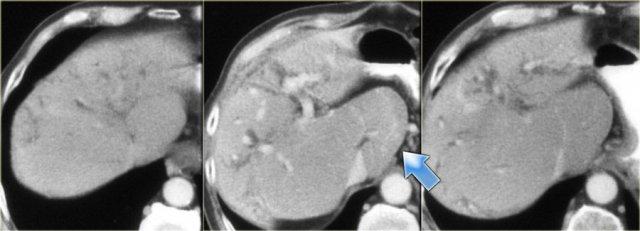

Các dấu hiệu CT giai đoạn muộn được thấy trong các hình ảnh bên trái.

Hãy quan sát các hình ảnh rồi tiếp tục đọc.

Các dấu hiệu bao gồm:

- Thay đổi hình thái xơ gan (mất thể tích thùy phải và thùy đuôi to ra (mũi tên))

- Giãn đường mật rõ hơn